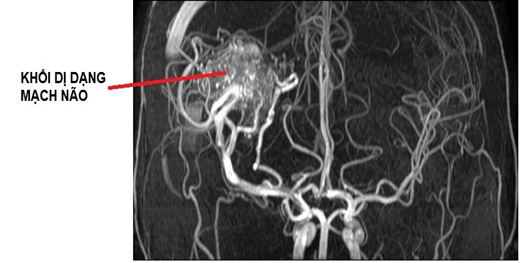

Hình ảnh dị dạng mạch não

Dị dạng mạch máu não (Arteriovenous malfor- mations of the brain–AVM) là sự bất thường về hình dạng, kích thước mạch máu hoặc nối thông trực tiếp động tĩnh mạch mà không thông qua mao mạch, không cấp máu cho não. Đây là một căn bệnh bẩm sinh và hết sức nguy hiểm, dị dạng mạch máu não có thể xuất hiện từ tuần thứ 4 đến tuần thứ 8 thai kỳ hoặc tự hình thành trong cuộc sống. Chiếm khoảng 2% những ca đột quỵ xuất huyết não hàng năm, thường xảy ra ở người trẻ tuổi mà trước đó không có nhiều triệu chứng đặc hiệu. Bệnh nhân thường vào viện với các triệu chứng của xuất huyết não, đau đầu, động kinh hoặc tình cờ phát hiện khi đi khám bệnh hoặc điều trị một bệnh khác.

Chẩn đoán dị dạng mạch máu não bằng chụp cộng hưởng từ sọ não (MRI sọ não); Cắt lớp vi tính (MSCT) từ 64 lát cắt chụp sọ não và mạch máu não có tiêm thuốc cản quang; Chụp mạch não số hóa xóa nền (DSA) để đánh giá chi tiết hình thái cấu trúc dị dạng mạch máu não đồng thời có thể điều trị can thiệp.